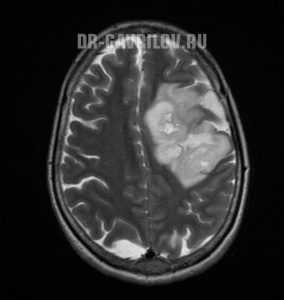

Глиома головного мозга — наиболее распространенная опухоль головного мозга, берущая свое начало из различных клеток глии. Клинические проявления глиомы зависят от ее расположения и могут включать головную боль, тошноту, вестибулярную атаксию, расстройство зрения, парезы и параличи, дизартрию, нарушения чувствительности, судорожные приступы и пр. Глиома головного мозга диагностируется по результатам МРТ головного мозга и морфологического исследования опухолевых тканей. Вспомогательное значение имеет проведение Эхо-ЭГ, ЭЭГ, ангиографии сосудов головного мозга, ЭЭГ, офтальмоскопии, исследования цереброспинальной жидкости, ПЭТ и сцинтиграфии. Общепринятыми способами лечения в отношении глиомы головного мозга являются хирургическое удаление, лучевая терапия, стереотаксическая радиохирургия и химиотерапия.

Глиома головного мозга встречается в 60% случаев опухолей головного мозга. Название «глиома» связано с тем, что опухоль развивается из глиальной ткани, окружающей нейроны головного мозга и обеспечивающей их нормальное функционирование. Глиома головного мозга представляет собой в основном первичную внутримозговую опухоль полушарий мозга. Она имеет вид розоватого, серовато-белого, реже темно-красного узла с нечеткими очертаниями. Глиома головного мозга может локализоваться в стенке желудочка мозга или в области хиазмы (глиома хиазмы). В более редких случаях глиома располагается в нервных стволах (например, глиома зрительного нерва). Прорастание глиомы головного мозга в мозговые оболочки или кости черепа наблюдается лишь в исключительных случаях.

Глиома головного мозга часто имеет округлую или веретенообразную форму, ее размер колеблется от 2-3 мм в диаметре до величины крупного яблока. В подавляющем большинстве случаев глиома головного мозга отличается медленным ростом и отсутствием метастазирования. Однако при этом она характеризуется настолько выраженным инфильтративным ростом, что границу опухоли и здоровых тканей не всегда удается найти даже при помощи микроскопа. Как правило, глиома головного мозга сопровождается дегенерацией окружающих ее нервных тканей, что зачастую приводит к несоответствию выраженности неврологического дефицита размерам опухоли.

Наиболее приемлемым способом диагностики глиомы головного мозга на сегодняшний день является МРТ головного мозга. При невозможности ее проведения может применяться МСКТ или КТ головного мозга, контрастная ангиография мозговых сосудов, сцинтиграфия. ПЭТ головного мозга дает сведения о метаболических процессах, по которым можно судить о скорости роста и агрессивности опухоли. Кроме того, с диагностической целью возможно проведение люмбальной пункции. При глиоме головного мозга анализ полученной цереброспинальной жидкости выявляет наличие атипичных (опухолевых) клеток.

Доля глиом в общей популяции опухолей головного мозга составляют около 60%. Чаще всего новообразования формируются в головном мозге, имеют первичный характер. Глиома ствола головного мозга диагностируется сравнительно редко. Цвет неоплазий от темно-красного до нежного розового, форма в большинстве случаев напоминает круг или веретено, но может иметь и неправильные очертания. Величина зависит от стадии болезни: от нескольких миллиметров до 10-14 см.